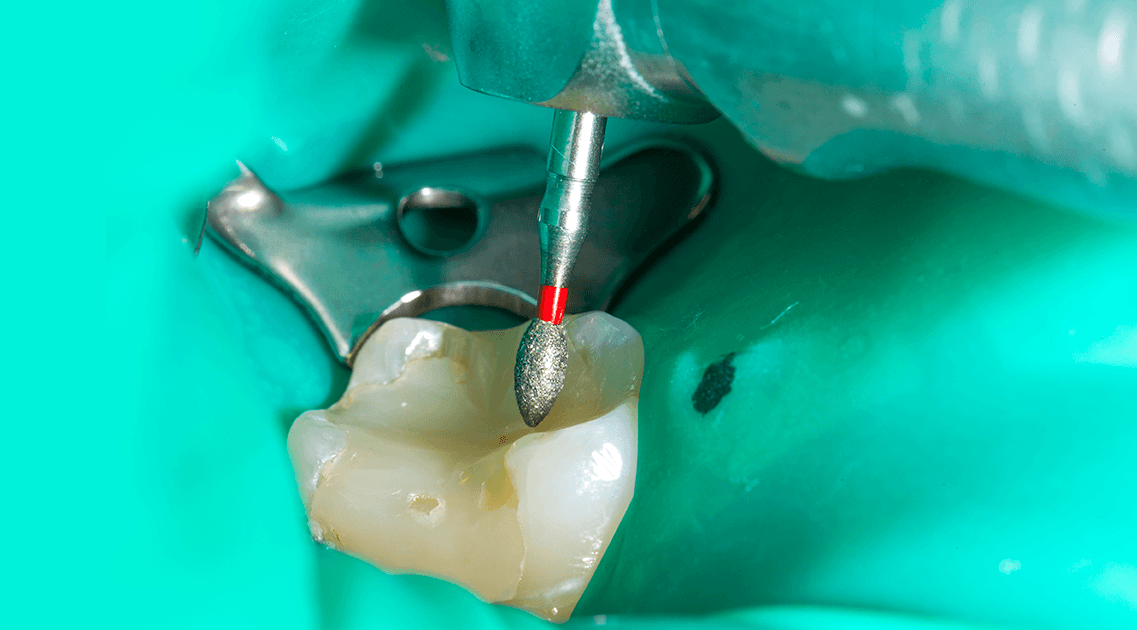

歯科治療においても、顕微鏡下で行う根管治療(マイクロエンド)や、歯冠・歯根破折治療、顕微鏡下で手術を行うマイクロサージェリー、その他歯を削ったり詰め物をする際に、想像をはるかに超える威力を発揮します。

このようにマイクロスコープは、歯科治療の分野においても非常に有効性の高い武器です。しかしマイクロスコープを使用しての治療には、高い治療技術が求められます。正しく使えなければ、いくら導入したからといって治療レベルが上がるわけではありません。

いままでの歯科治療の多くは、肉眼と手指感覚で行われてきました。しかし人間の目には限界があり、虫歯(細菌)の取り残しや、精度の甘い部位からの細菌の侵入などにより、一度治療したところが再発してしまうケースが残念ながら多く見受けられます。